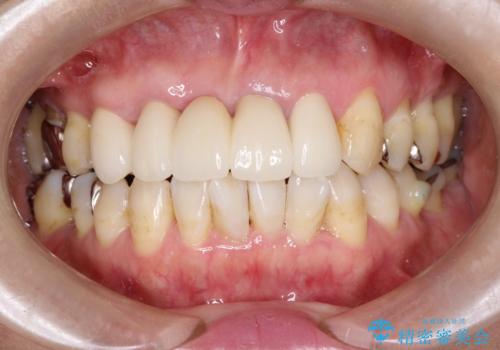

金属をセラミックにしたい、根管治療も行ったケース

この際全てをしっかりと治療したい 総合歯科治療

奥歯の目立つ銀歯を白くしたい